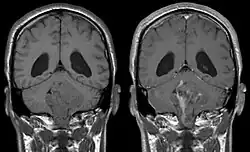

Durch ihre Lokalisation in der Nähe der Ventrikel behindern Ependymome häufig den Fluss der Cerebrospinalflüssigkeit, was zu einer Erhöhung des Hirndrucks führen kann. Daraus können sich anhaltende Kopfschmerzen, Übelkeit und Erbrechen sowie ein Hydrozephalus ergeben.

In Kernspintomografie-Aufnahmen des Kopfes stellt sich das Ependymom typischerweise als umschriebene Läsion mit Bezug zum Ventrikelsystem dar, die ein heterogenes Signalmuster mit zystischen Anteilen aufweist sowie mäßig und girlandenartig Kontrastmittel anreichert. In 50 % sind in der Schnittbildgebung Verkalkungen zu erkennen. Zytologische Untersuchung der Cerebrospinalflüssigkeit sowie Tumorbiopsie können zur Diagnosefindung beitragen.